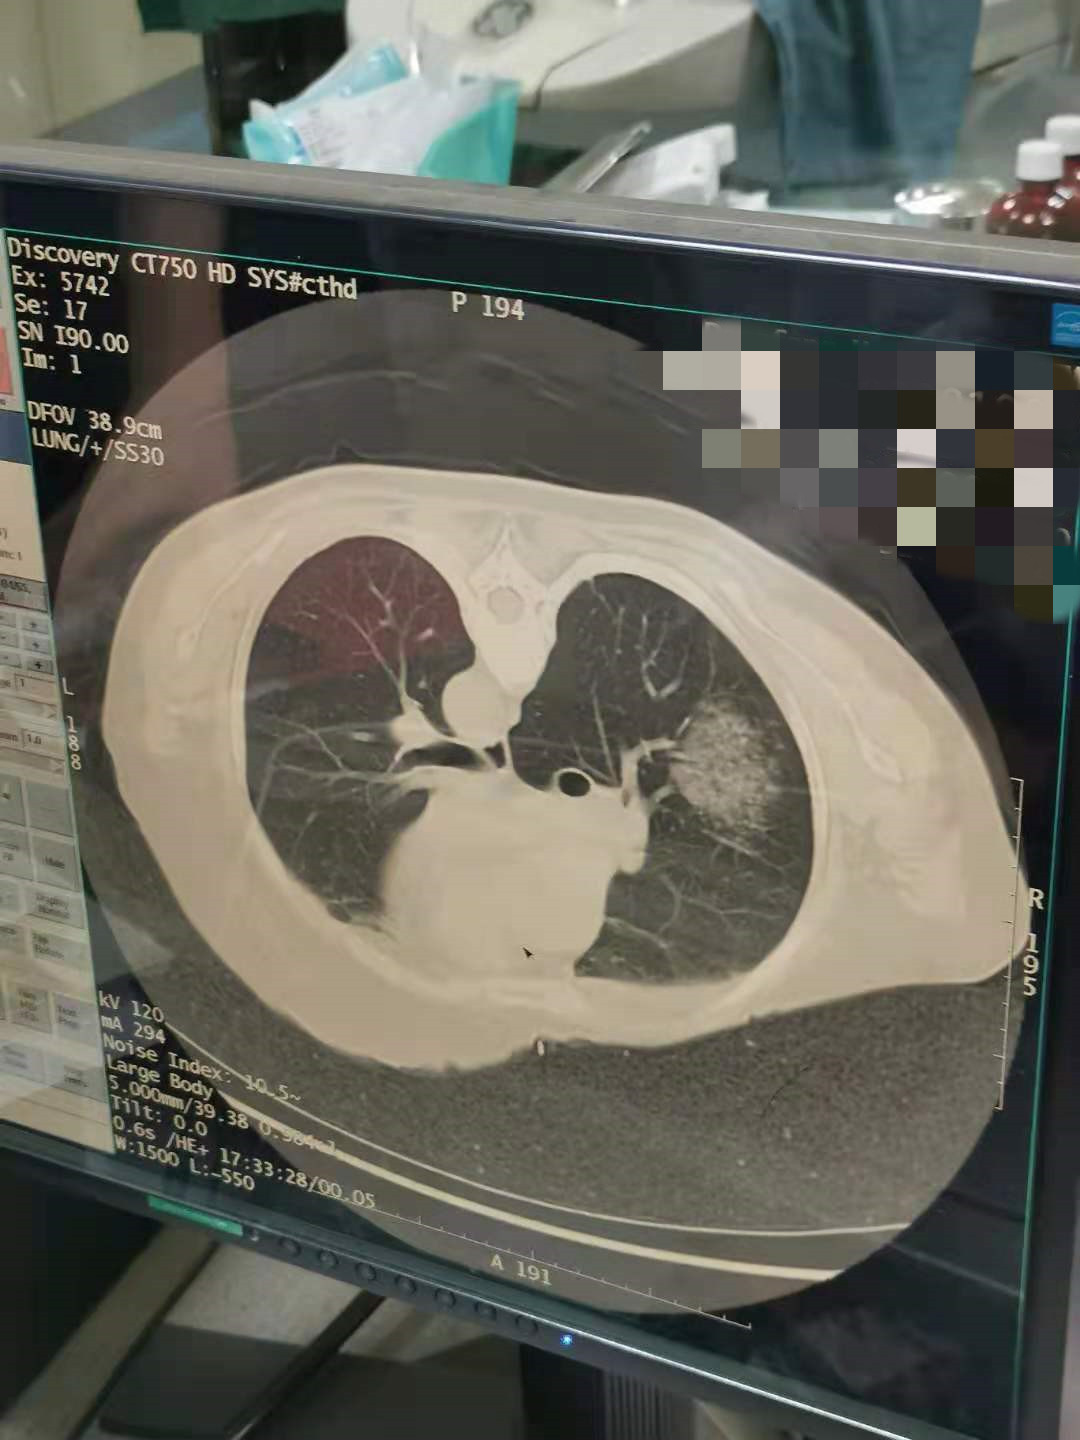

2021年7月份肺部氩氦刀手术